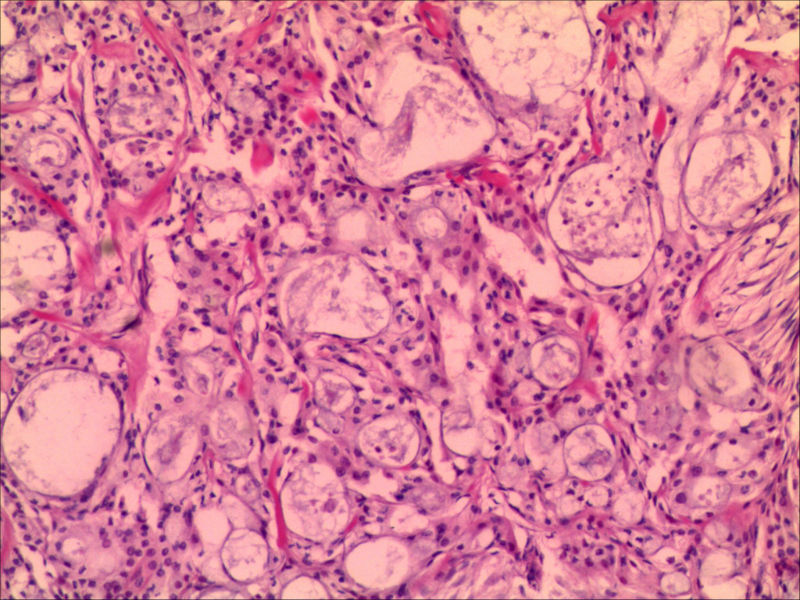

右下颌肿物女26岁 大家帮帮看看

典型的黏液表皮样癌,低度恶性。

本例可以看到典型的产粘液细胞、鳞状细胞、中间细胞和透明细胞,因为产粘液细胞多,甚至形成粘液湖,加之包块似有包膜,分界清楚,应该考虑粘液表皮样癌(低度恶性)。